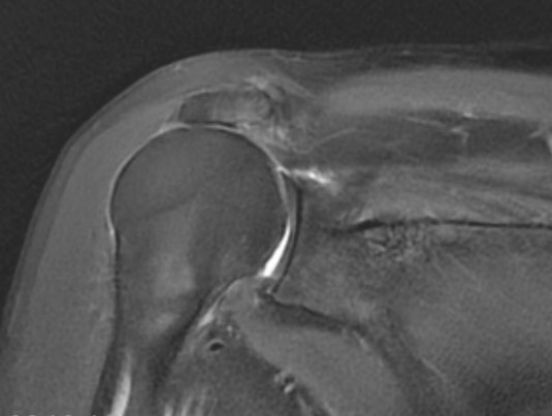

• 反肩置换术:高龄肩袖撕裂伴假瘫的“治疗新径”

丁少华

宁波市医疗中心李惠利医院